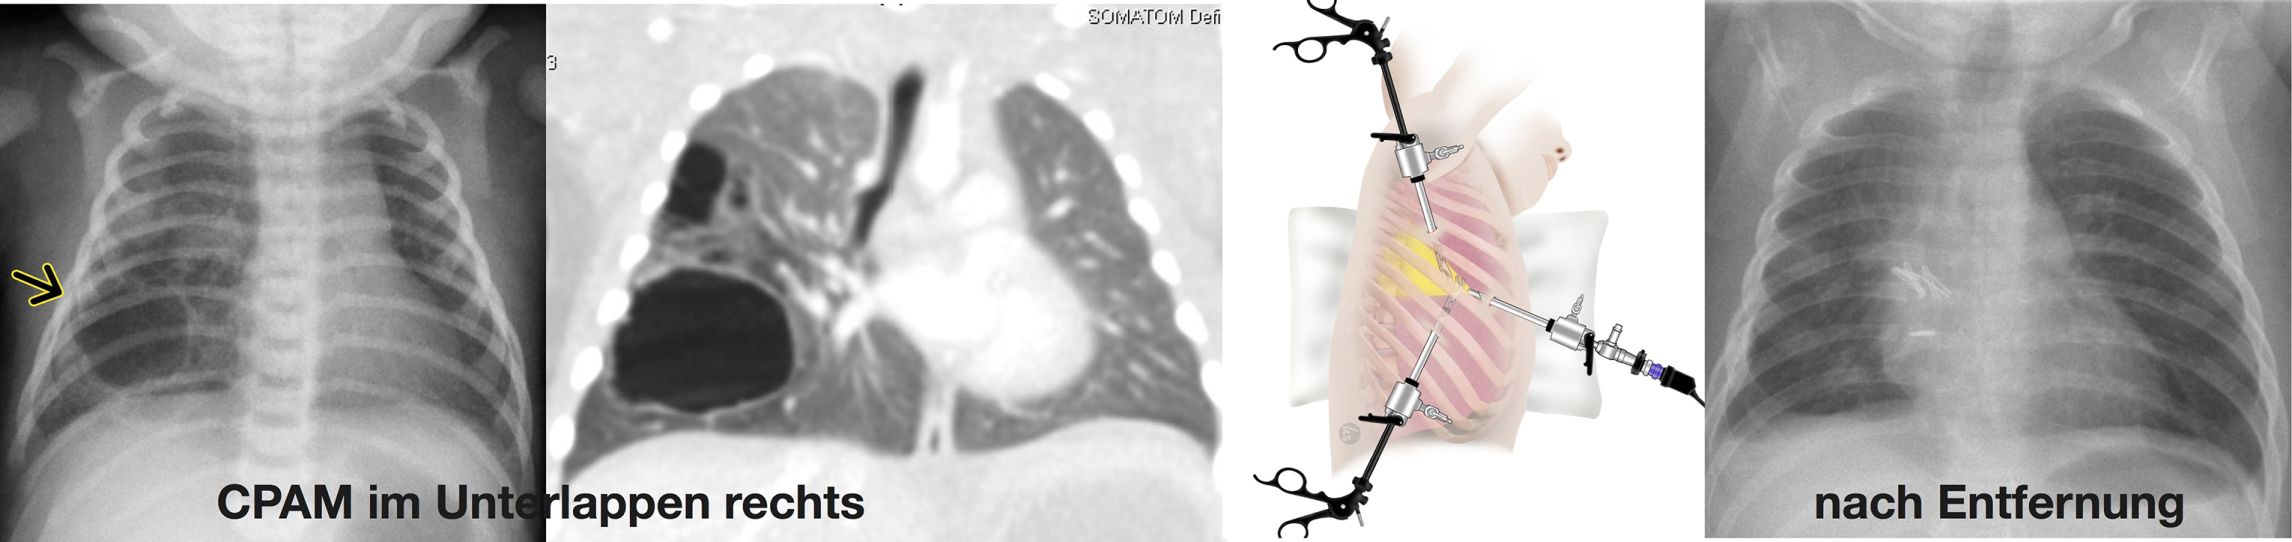

• CPAM (Congential Pulmonary Airway Malformation) früher als Zystische Malformation der Lunge (CPAM) bezeichnet: Hier handelt es sich um eine zunächst gutartige Veränderung eines Teils der Lunge, durch fehlerhafte Entwicklung in der Embryonalzeit. Der betroffene Lungenabschnitt weist teilweise solide und vor allem zystische Veränderungen des Lungengewebes auf (Abbildung).

Da Fehlbildungen der Lunge vor allem zur Beeinträchtigung der umgebenden gesunden Lunge führen können, muss häufig eine Entfernung erfolgen. Damit wird erreicht, dass die gesunde Lunge sich normal weiter entwickeln kann. Unsere jahrzehntelange Erfahrung auf diesem Gebiet gewährleistet, dass sowohl offen chirurgische als auch minimalinvasive Resektionen schon beim Neugeborenen nach entsprechender Patientenselektion und Indikationsstellung sicher durchgeführt werden.

Lungenchirurgie: Abb. links: CPAM im Unterlappen rechts. Abb. rechts: nach Entfernung

Lungenchirurgie: Linke Seite der Abbildung: CPAM im Unterlappen rechts. Rechte Seite der Abbildung: nach Entfernung.